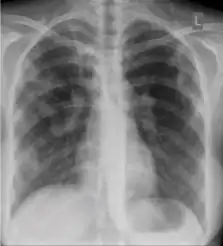

Chest x-ray of Ghon's complex of active tuberculosis